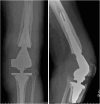

Distal Femoral Replacement With a Metaphyseal Sleeve: Outcomes and Risk Factors for Subsidence

In this study, we report on the outcomes of our experience using a metaphyseal sleeve with a distal femoral replacement (DFR) and review the risk factors for sleeve subsidence over a 3 year period.